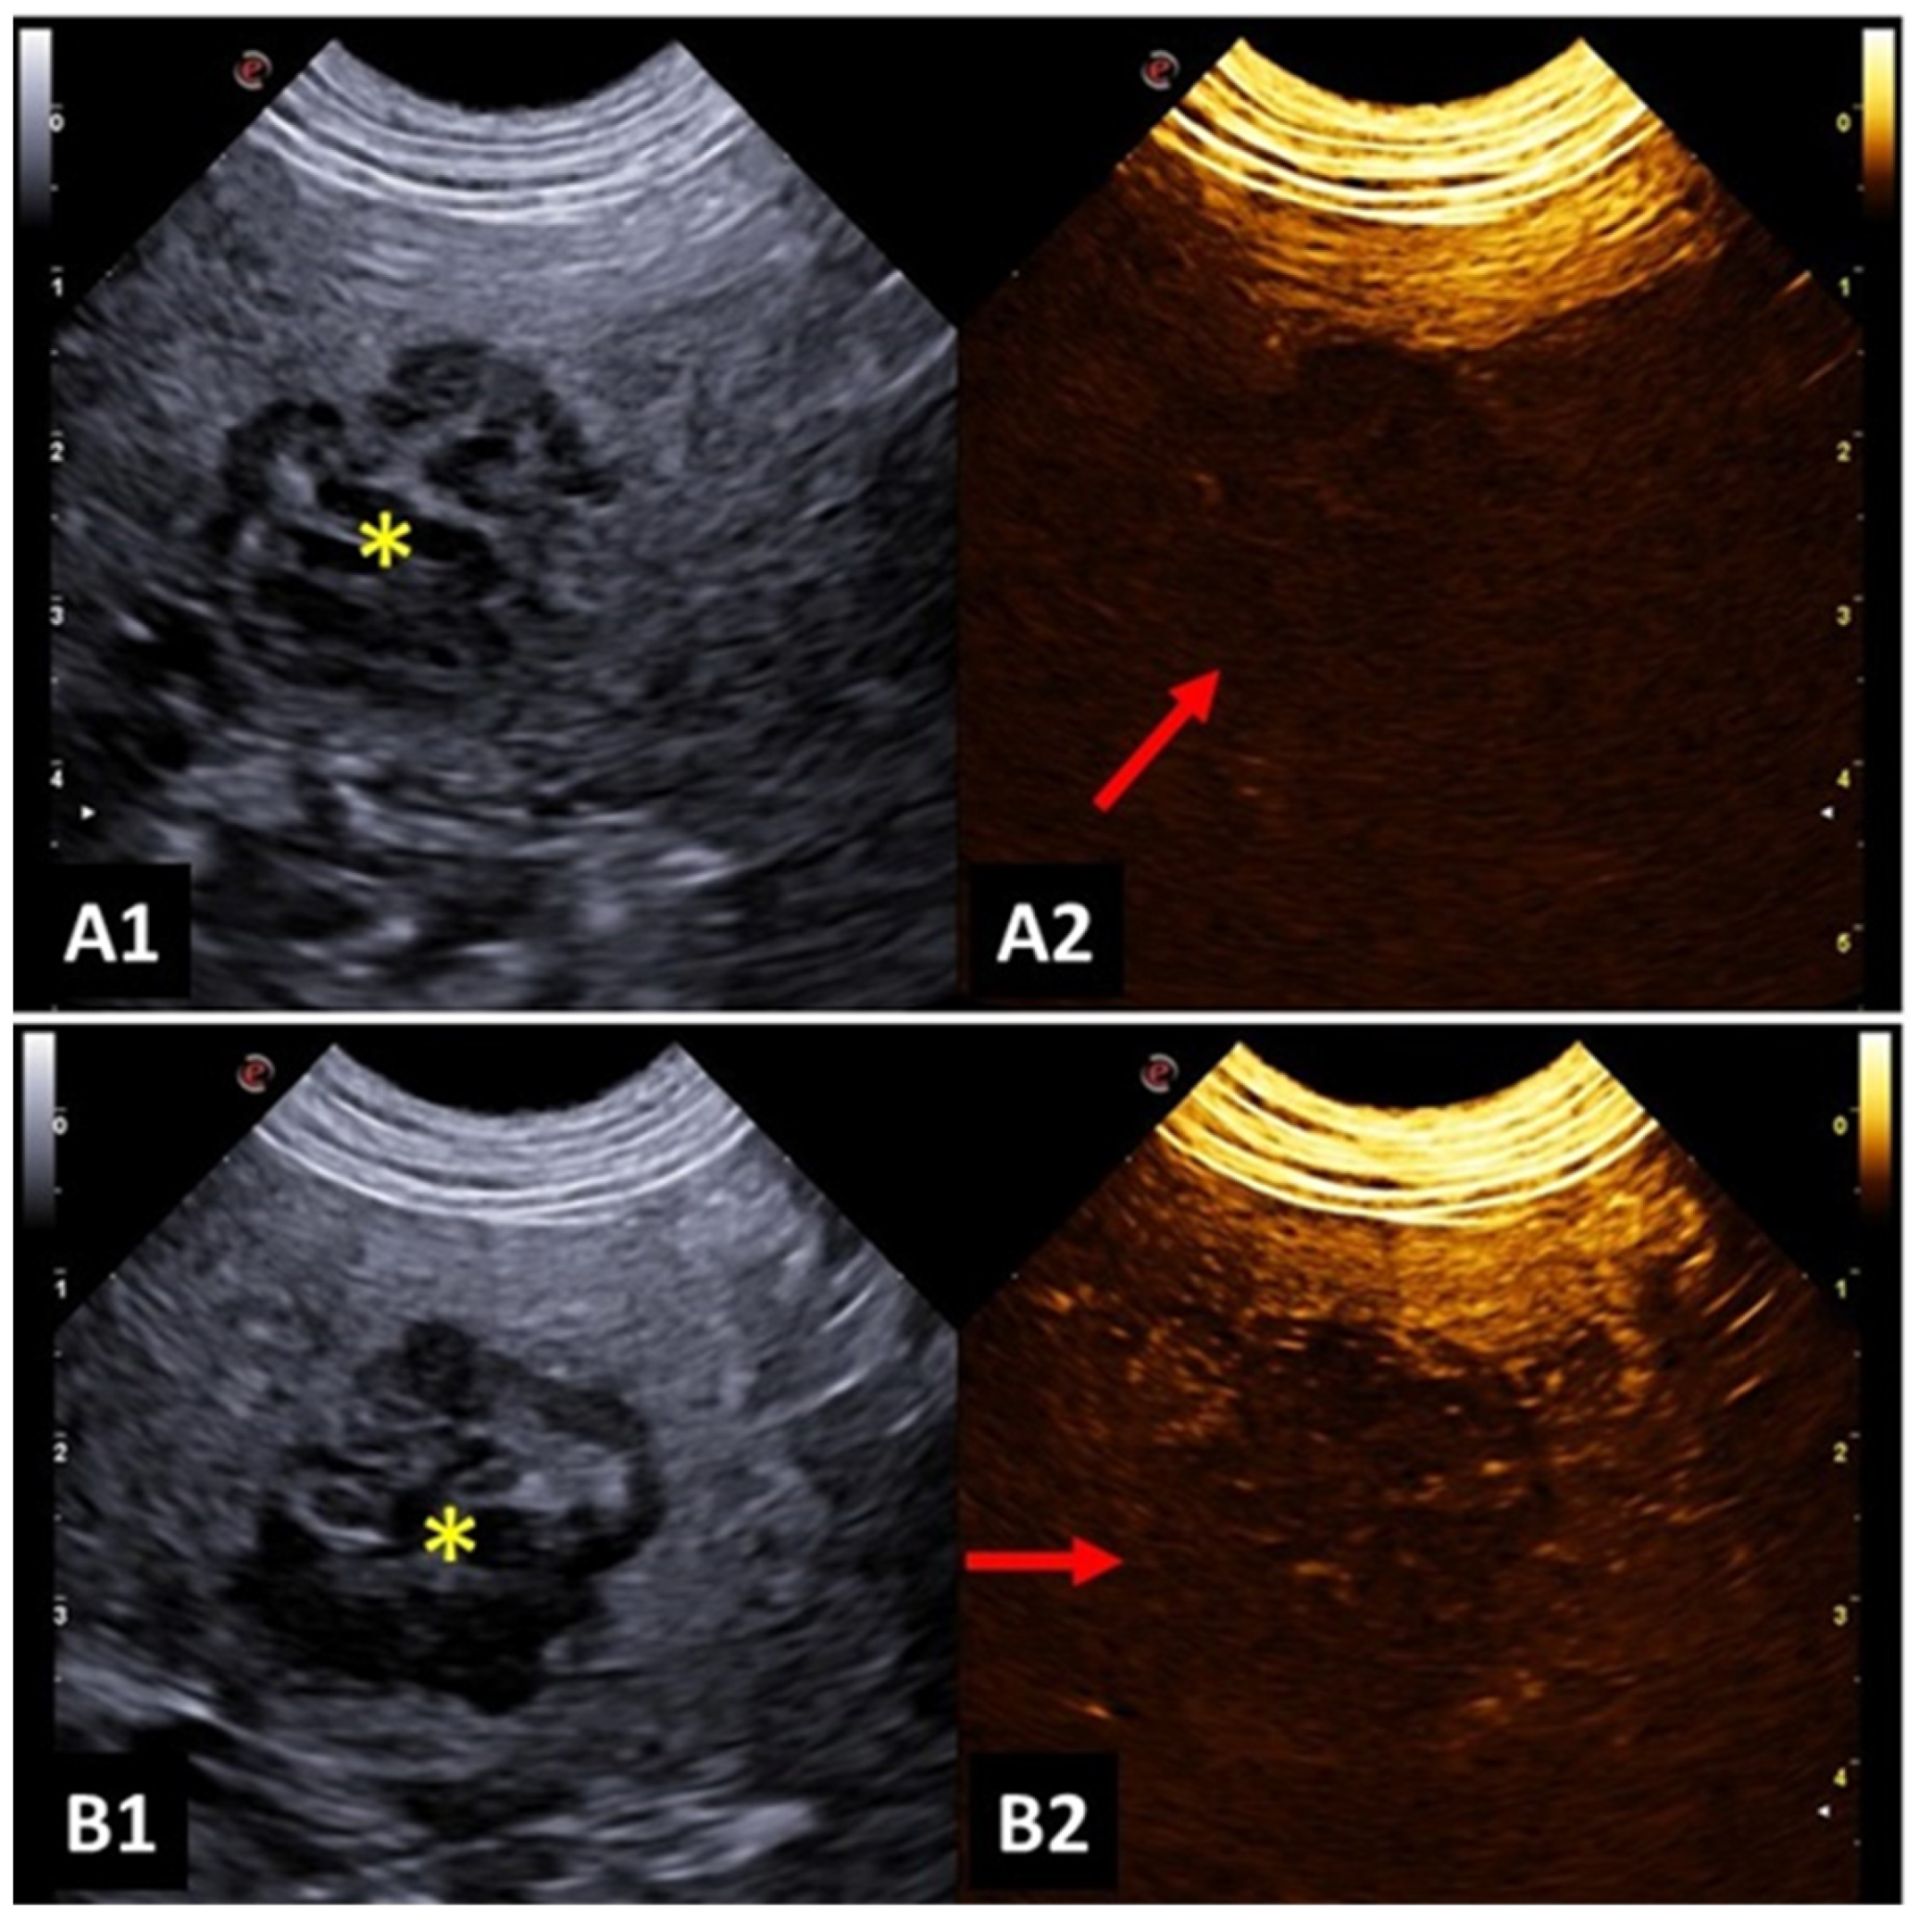

4.5. Spleen